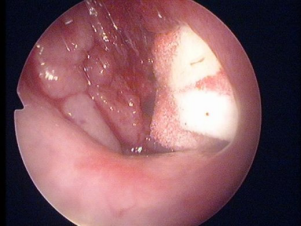

腺样体肥大内窥镜图片

腺样体肥大堵塞后鼻孔